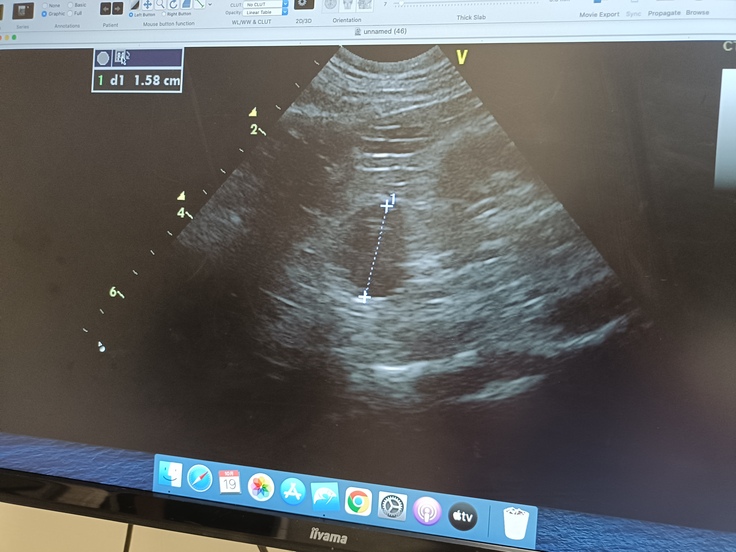

今日のエコー検査で、左側だけじゃなく右側まで形がイビツになっており、1.5mmの腫瘍が見つかりました。

また、脾臓の中にも小さな黒丸があり、約7mmの、こちらも腫瘍だと思われます。